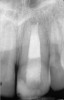

Fig 3. Postoperative radiograph.

Figure 3

Clinical procedure: If apical bone loss is present (Figure 1) a collagen/gelatin sponge (eg, Gelfoam®, Pfizer Inc., www.pfizer.com) can be placed apically so that the MTA can be delivered to the desired working length. (Any other surgical resorbable sponge would also work, such as OraPlug® [Salvin Dental Specialties, www.salvin.com], Surgifoam® [Midwest Dental, www.mwdental.com], or Surgispon® [Aegis Lifesciences, www.surgispon.com]). This is done by taking a small piece (2 mm x 2 mm) of the resorbable sponge and pushing it down to and through the root apex with an endodontic file. Once this is done, MTA is packed down the canal with a custom-fitted cone. The clinician can use a rubber stopper on the gutta-percha cone to know the exact length of MTA placed in the apical third (Figure 2). Once the apical third is sealed with 3 mm to 5 mm of MTA, the remaining coronal canal space can be back-filled using a warm gutta-percha technique (Figure 3).